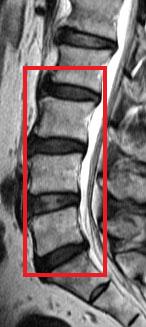

Low back pain affects every population worldwide, and is a leading cause of ill-health and sick leave in the working population of Hong Kong. One of the major causes of low back pain is degeneration of the joints of the spine, known as the intervertebral discs. A cohort study conducted by the Department of Orthopaedics & Traumatology at The University of Hong Kong Li Ka Shing Faculty of Medicine reveals that being obese in adulthood doubles the likelihood of having disc degeneration and developing more severe forms of the condition than those of normal weight. These findings are of public health concern and were published in the latest issue of the authoritative journal Arthritis and Rheumatism.

The current study was a cross-sectional assessment of adults from this cohort who were 21 years of age and older. A total of 2,599 individuals were assessed with magnetic resonance imaging (MRI). Amongst them, 27% (n=709) did not have disc degeneration while 73% (n=1,890) had. Of the subjects who have disc degeneration, 7% were underweight, 48% were in the normal weight range, 36% were overweight, and 9% were obese. Overweight and obese individuals were also found to have a greater extent and severity of disc degeneration in comparison to those individuals of normal weight or underweight.